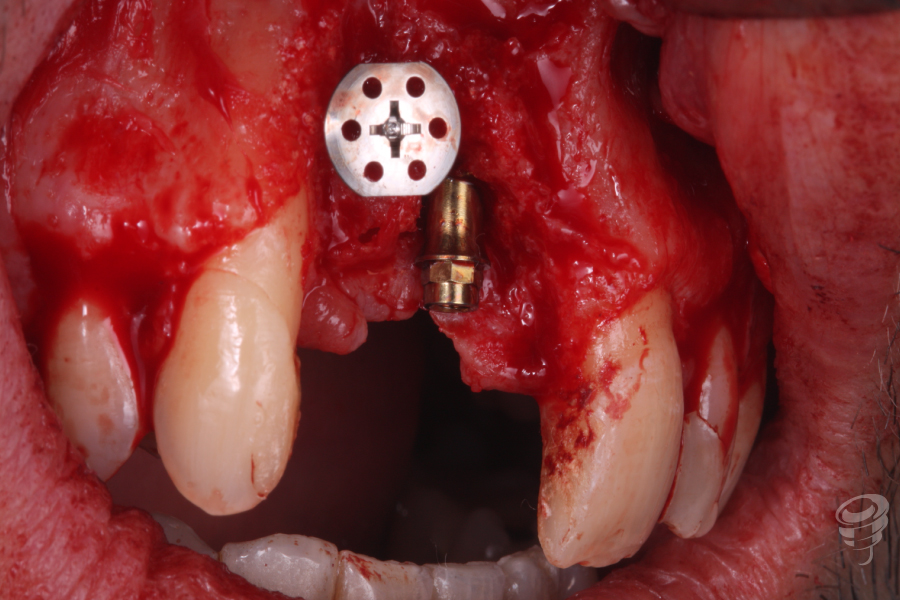

En este caso clínico el paciente presenta un implante colocado en una posición errónea en el sector anterior.

Acude a consulta demandando una solución para un implante situado en posición 12. Este implante nunca se ha rehabilitado debido a su mala situación clínica y radiográfica.

Realizamos un estudio con un CBCT de la zona. En los cortes seccionales se visualiza el implante en una posición muy vestibular, fuera del marco óseo y una imagen radiolúcida rodeando el implante.

- Realizamos la explantación del implante colocado en una posición anómala con un extractor de implantes Galimplant de una manera muy simple, ya que no estaba totalmente osteointegrado.

Colocamos un tornillo de Tent Pole en la zona del defecto creado por el implante en 12 para conseguir un relleno óseo adecuado.